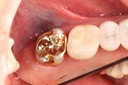

Mark Chun #17 model

Mark Chun #17 casting